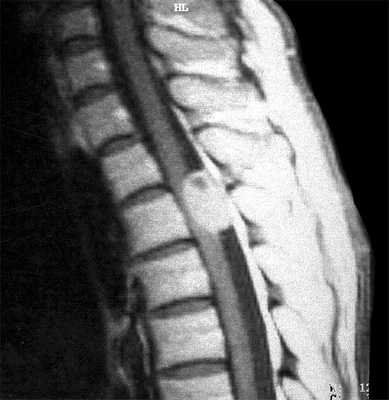

МРТ позвоночника. Т2-взвешенная сагиттальная МРТ. Компрессия спинного мозга. Цветовая обработка изображения.

Изменение клинической симтоматики в хроническом периоде травмы, такое как наростание симптомов миелопатиии, повышение уровня неврологического дефицита, боли и увеличение мышечного спазма служат признаками развития поздних осложнений. Для оценки их характера показана МРТ позвоночника. Вместе с тем, надо иметь ввиду, что у таких пациентов часто имплантированы металлические конструкции, создающие артефакты. Осторожности требует исследование пациентов с нейростимуляторами.

Типичными для хронической травмы изменениями при МРТ позвоночника являются миеломаляция, киста и атрофия спинного мозга. Посттравматический отёк спинного мозга приводит к его ишемии, с последующей демиелинизаций и глиозом. Патогенетической основой формирования кисты служит интрамедуллярная гематома. При ее резорбции остаётся локальная киста. Соединение кисты со спинномозговым каналом приводит к его расширению, а адгезия к нарушению оттока ликвора.

Сирингомиелитические кисты как отдалённое последствие спинальной травмы встречаются у 3-4% пациентов с неврологическими нарушениями. В целом, они относятся к отдалённым последствиям трамы, хотя известны случаи раннего формирования сирингомиелитических кист. Чаще кисты выявляются при МРТ грудном отделе спинного мозга. Замечена связь сирингомиелитических кист с деформацией позвоночного канала и посттравматическим его стенозом. В отличие от истинной сирингомиелии они развиваются на фоне атрофии и обычно не сопровождаются вздутием спинного мозга. Кисты наблюдаются с одинаковой частотой как выше, так и ниже уровня травмы. Протяжённость кисты может быть любой. Содержимое кисты обычно ликворное, но бывает и с примесью белка, что повышает сигнал от её содержимого на Т1-зависимых МРТ. На Т2-зависимых МРТ в кисте могут быть зоны потери сигнала, что отражает повышенное давление внутри неё. Отмечено, что дренаж кист в этих случаях наиболее эффективен. Изредка при МРТ в кистах встречаются перегородки.

МРТ шейного отдела позвоночника. Кистозно-атрофические изменения. Т2-взвешенная сагиттальная МРТ.